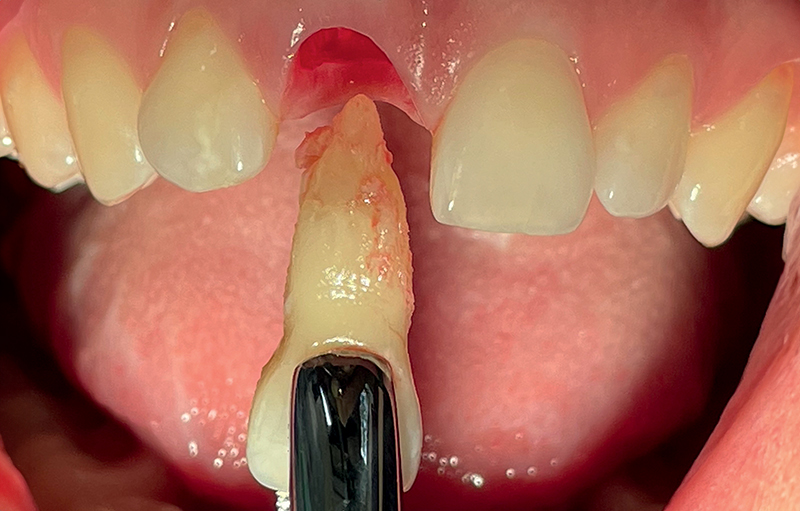

Fig. 11 (caso 3) - Quadro clinico iniziale

Caso 3: Un paziente maschio subiva un trauma durante l'infanzia e si presentava con una fistola associata al dente 11 e un difetto della cresta alveolare vestibolare. Il paziente era sottoposto a posizionamento immediato di un impianto SDS. In questo caso, l'aumento veniva combinato con il prelievo di tessuto connettivo subepiteliale (SCTG) dal palato, attraverso una singola incisione, tunnellizzazione buccale e inserimento dell’innesto. I successivi appuntamenti di follow-up rivelavano il successo della preservazione della cresta alveolare vestibolare, e della guarigione dei tessuti molli attorno all'impianto. L'osteointegrazione avveniva senza problemi e si poteva iniziare la pianificazione della corona definitiva. Questo caso era seguito per 5 anni e anche dopo questo periodo il contorno alveolare era estremamente soddisfacente. La guarigione e la gestione dei tessuti molli erano adeguate, suggerendo come l'applicazione dell'innesto di tessuto connettivo abbia contribuito positivamente al risultato estetico (Fig. 11-17).